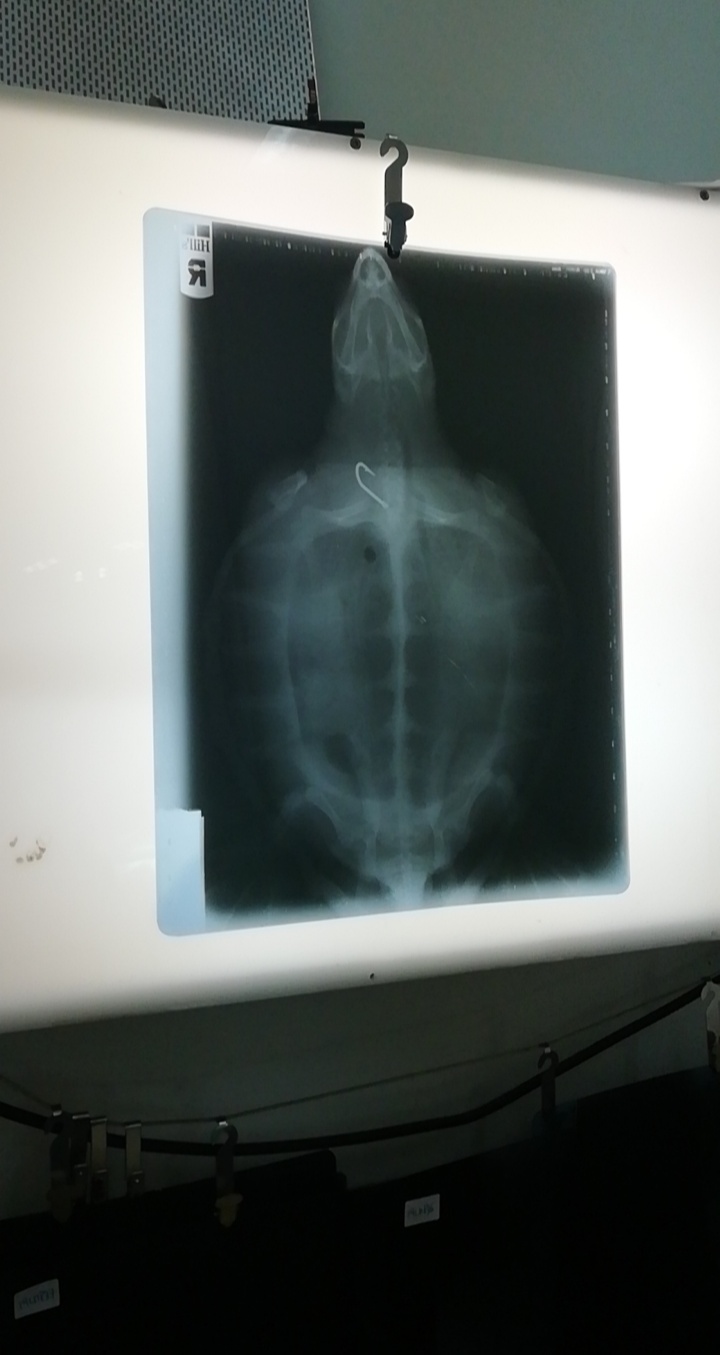

Inizialmente, si è ipotizzato che l’animale fosse nato senza pinne, poiché i moncherini non presentavano segni o ferite recenti. Le prime visite hanno però evidenziato la presenza di un amo da pesca nell’esofago ed è stato approntato un intervento chirurgico per la rimozione dello stesso, eseguito dal professor Antonio Di Bello, del Dipartimento di Medicina Veterinaria dell’Università di Bari, esperto noto a livello mondiale nella chirurgia delle tartarughe marine, animali per cui necessita una conoscenza specifica. Secondo gli esperti, quindi, la presenza dell’amo potrebbe spiegare la perdita delle pinne anteriori, forse da imputare alla lenza che, attorcigliatasi attorno alle estremità, avrebbe col tempo lesionato le pinne a tal punto da staccarle dal corpo. I moncherini si sarebbero quindi perfettamente cicatrizzati. Il resto della lenza invece, che a causa della costante frizione ha procurato delle ulcerazioni all’esofago, avrebbe raggiunto il punto di rottura ed è andata perduta.